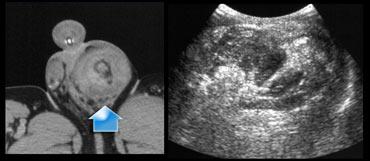

Bên trái là một trường hợp phức tạp.

Siêu âm cho thấy một tràn máu màng tinh hoàn lớn.

Có nghi ngờ liệu cấu trúc tăng âm đó có thực sự là tinh hoàn hay không.

MRI đã được thực hiện và không tìm thấy mô tinh hoàn, vì vậy chúng ta phải kết luận rằng cấu trúc tăng âm này là kết quả của một khối máu tụ mới.

Bên trái là một bệnh nhân khác bị vỡ tinh hoàn, được phát hiện trên CT bụng.

Trên siêu âm có một vùng không đồng nhất lớn không xác định được tinh hoàn do vỡ.